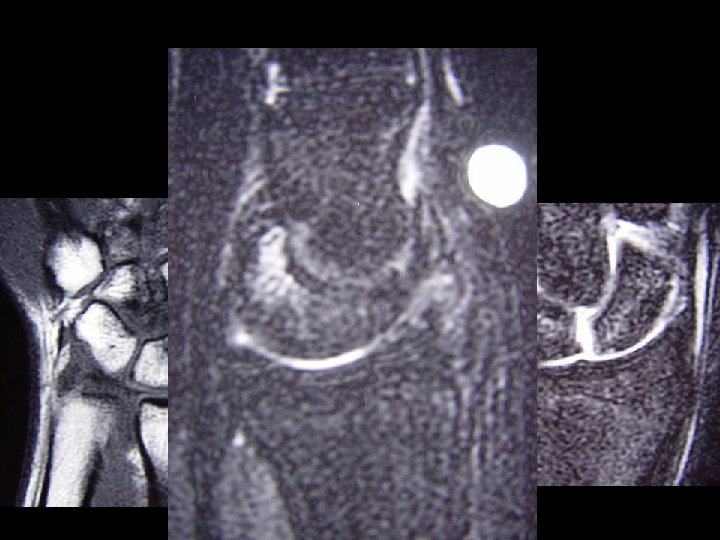

Eur Radiol. 2006 Mar 1

Eur Radiol. 2006 Mar